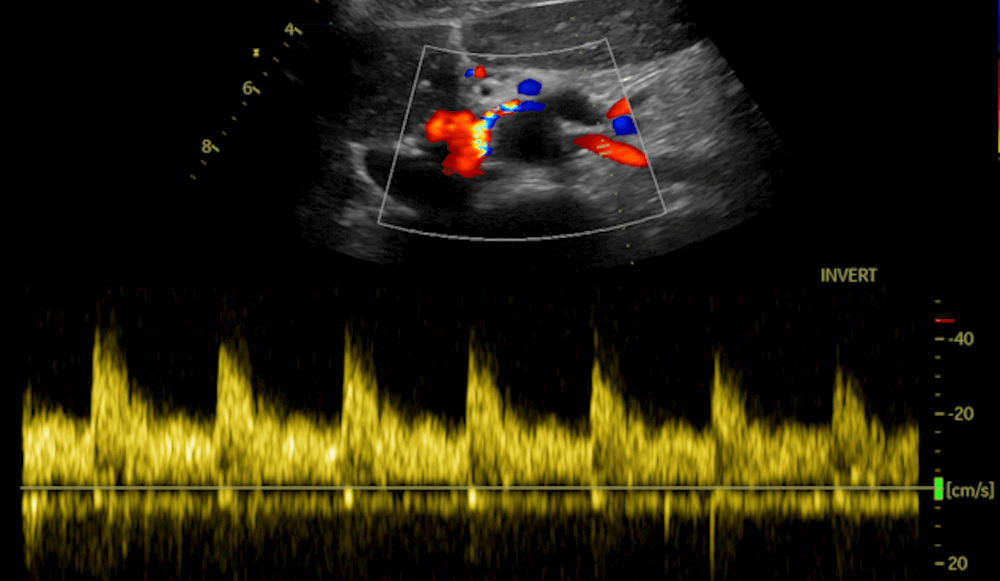

The flaws, publicly reported this week by researchers at Nozomi Networks, affect the Vivid T9 ultrasound system and its pre-installed Common Service Desktop web application as well as the EchoPAC software.

The Vivid T9 is built for cardiac imaging, but it can also be used as a general-purpose ultrasound system for other parts of the body. Common Service Desktop is an application that facilitates administrative tasks like password changes, logs and more. EchoPAC is a tool doctors use to look at ultrasound images.